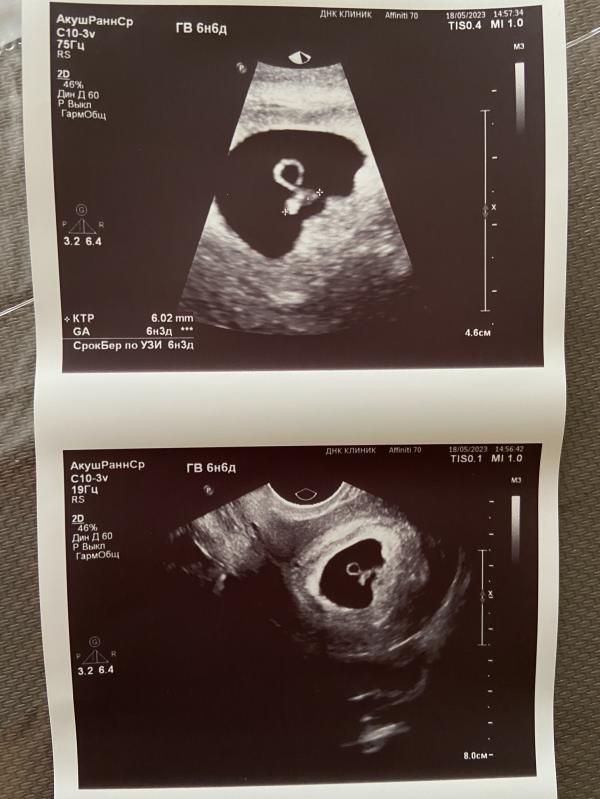

Пя 22 мм, СБ 118, КТР 6,2, ЖМ 2,6 - все в норме? Акушерский срок 6.6, по эмбриону 6.3 - догонит?

И вот что мы имеем🙏🏼

Пя-22мм

Сб-118

Ктр-6,2

Жм-2,6

Акушерских -6.6

6.3 по эмбриону(догонят , ранее было на неделю меньше)

Вроде все окей ?)